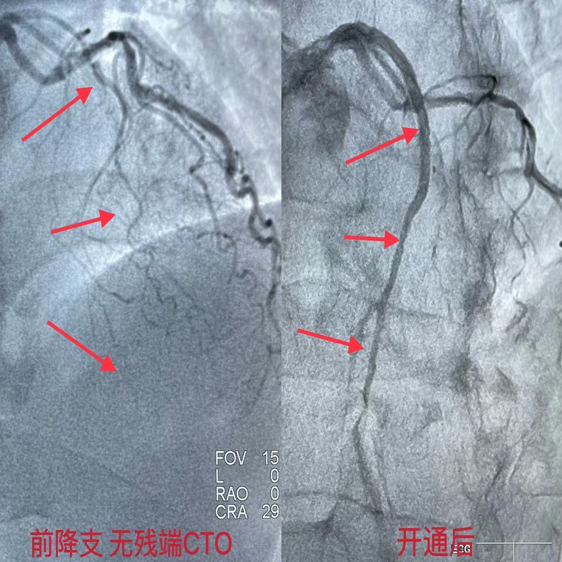

该患者于10天前,于我院开通前降支无残端CTO,右冠脉迂曲、弥漫长病变伴严重钙化,此次在OCT指导下,Guidezilla延长导管辅助下,送入Shockwave IVL冲击波球囊于病变处予8个周期80个脉冲的预处理后顺利植入支架,复查OCT结果满意,未见支架膨胀不全及贴壁不良。